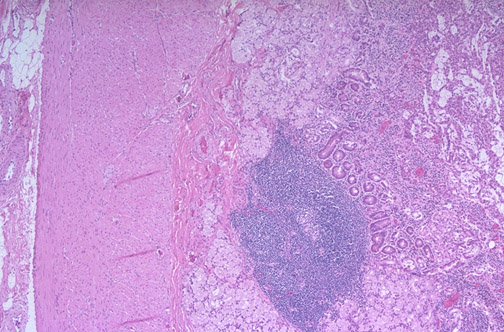

| This is the low power microscopic appearance of the duodenum with the mucosa, the submucosa, the muscularis with both the inner circular as well as the outer longitudinal coats of smooth muscle. There is a lymphoid nodule in the submucosa, characteristic for gut-associated lymphoid tissue. Characteristic for duodenum are submucosal Brunner's glands. There is an outer serosa. The myenteric plexus is found between circular and longitudinal muscle bundles, while the Meissner's plexus is found in the submucosa. |